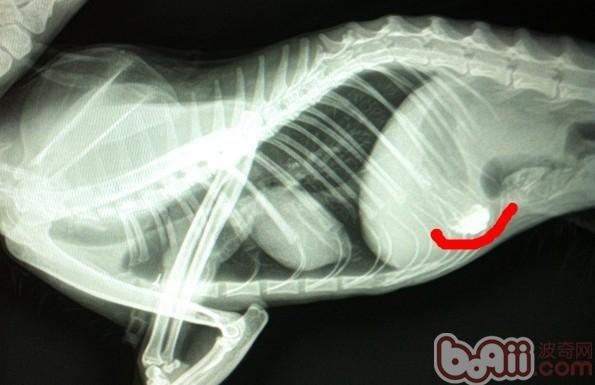

此為上文中提到的貓咪誤食的大閘蟹扎線,看似柔軟,但是這樣的線粗且長,經過腸道蠕動后更容易在腸道中堵塞,圖片中的線在鋇餐造影以后確定位置,手術治療,10天后貓咪逐漸恢復正常。

此片攝于患貓灌入鋇餐20小時后,正常情況下,鋇餐應完全通過胃區,通過腸道,應幾乎排空,顯然此片中胃區任有少量殘余液體,腸道內幾乎排空,反映出雖然消化道沒有完全堵塞,但胃排空較慢,腸道蠕動減慢,因此貓為長毛貓,消瘦,主人常年在外缺乏管理,不能提供足夠的病情資料,與主人溝通后,采取保守治療,通過支持療法和食物緩瀉療法,此貓逐漸排除體內伴有大量毛發的干燥積便。